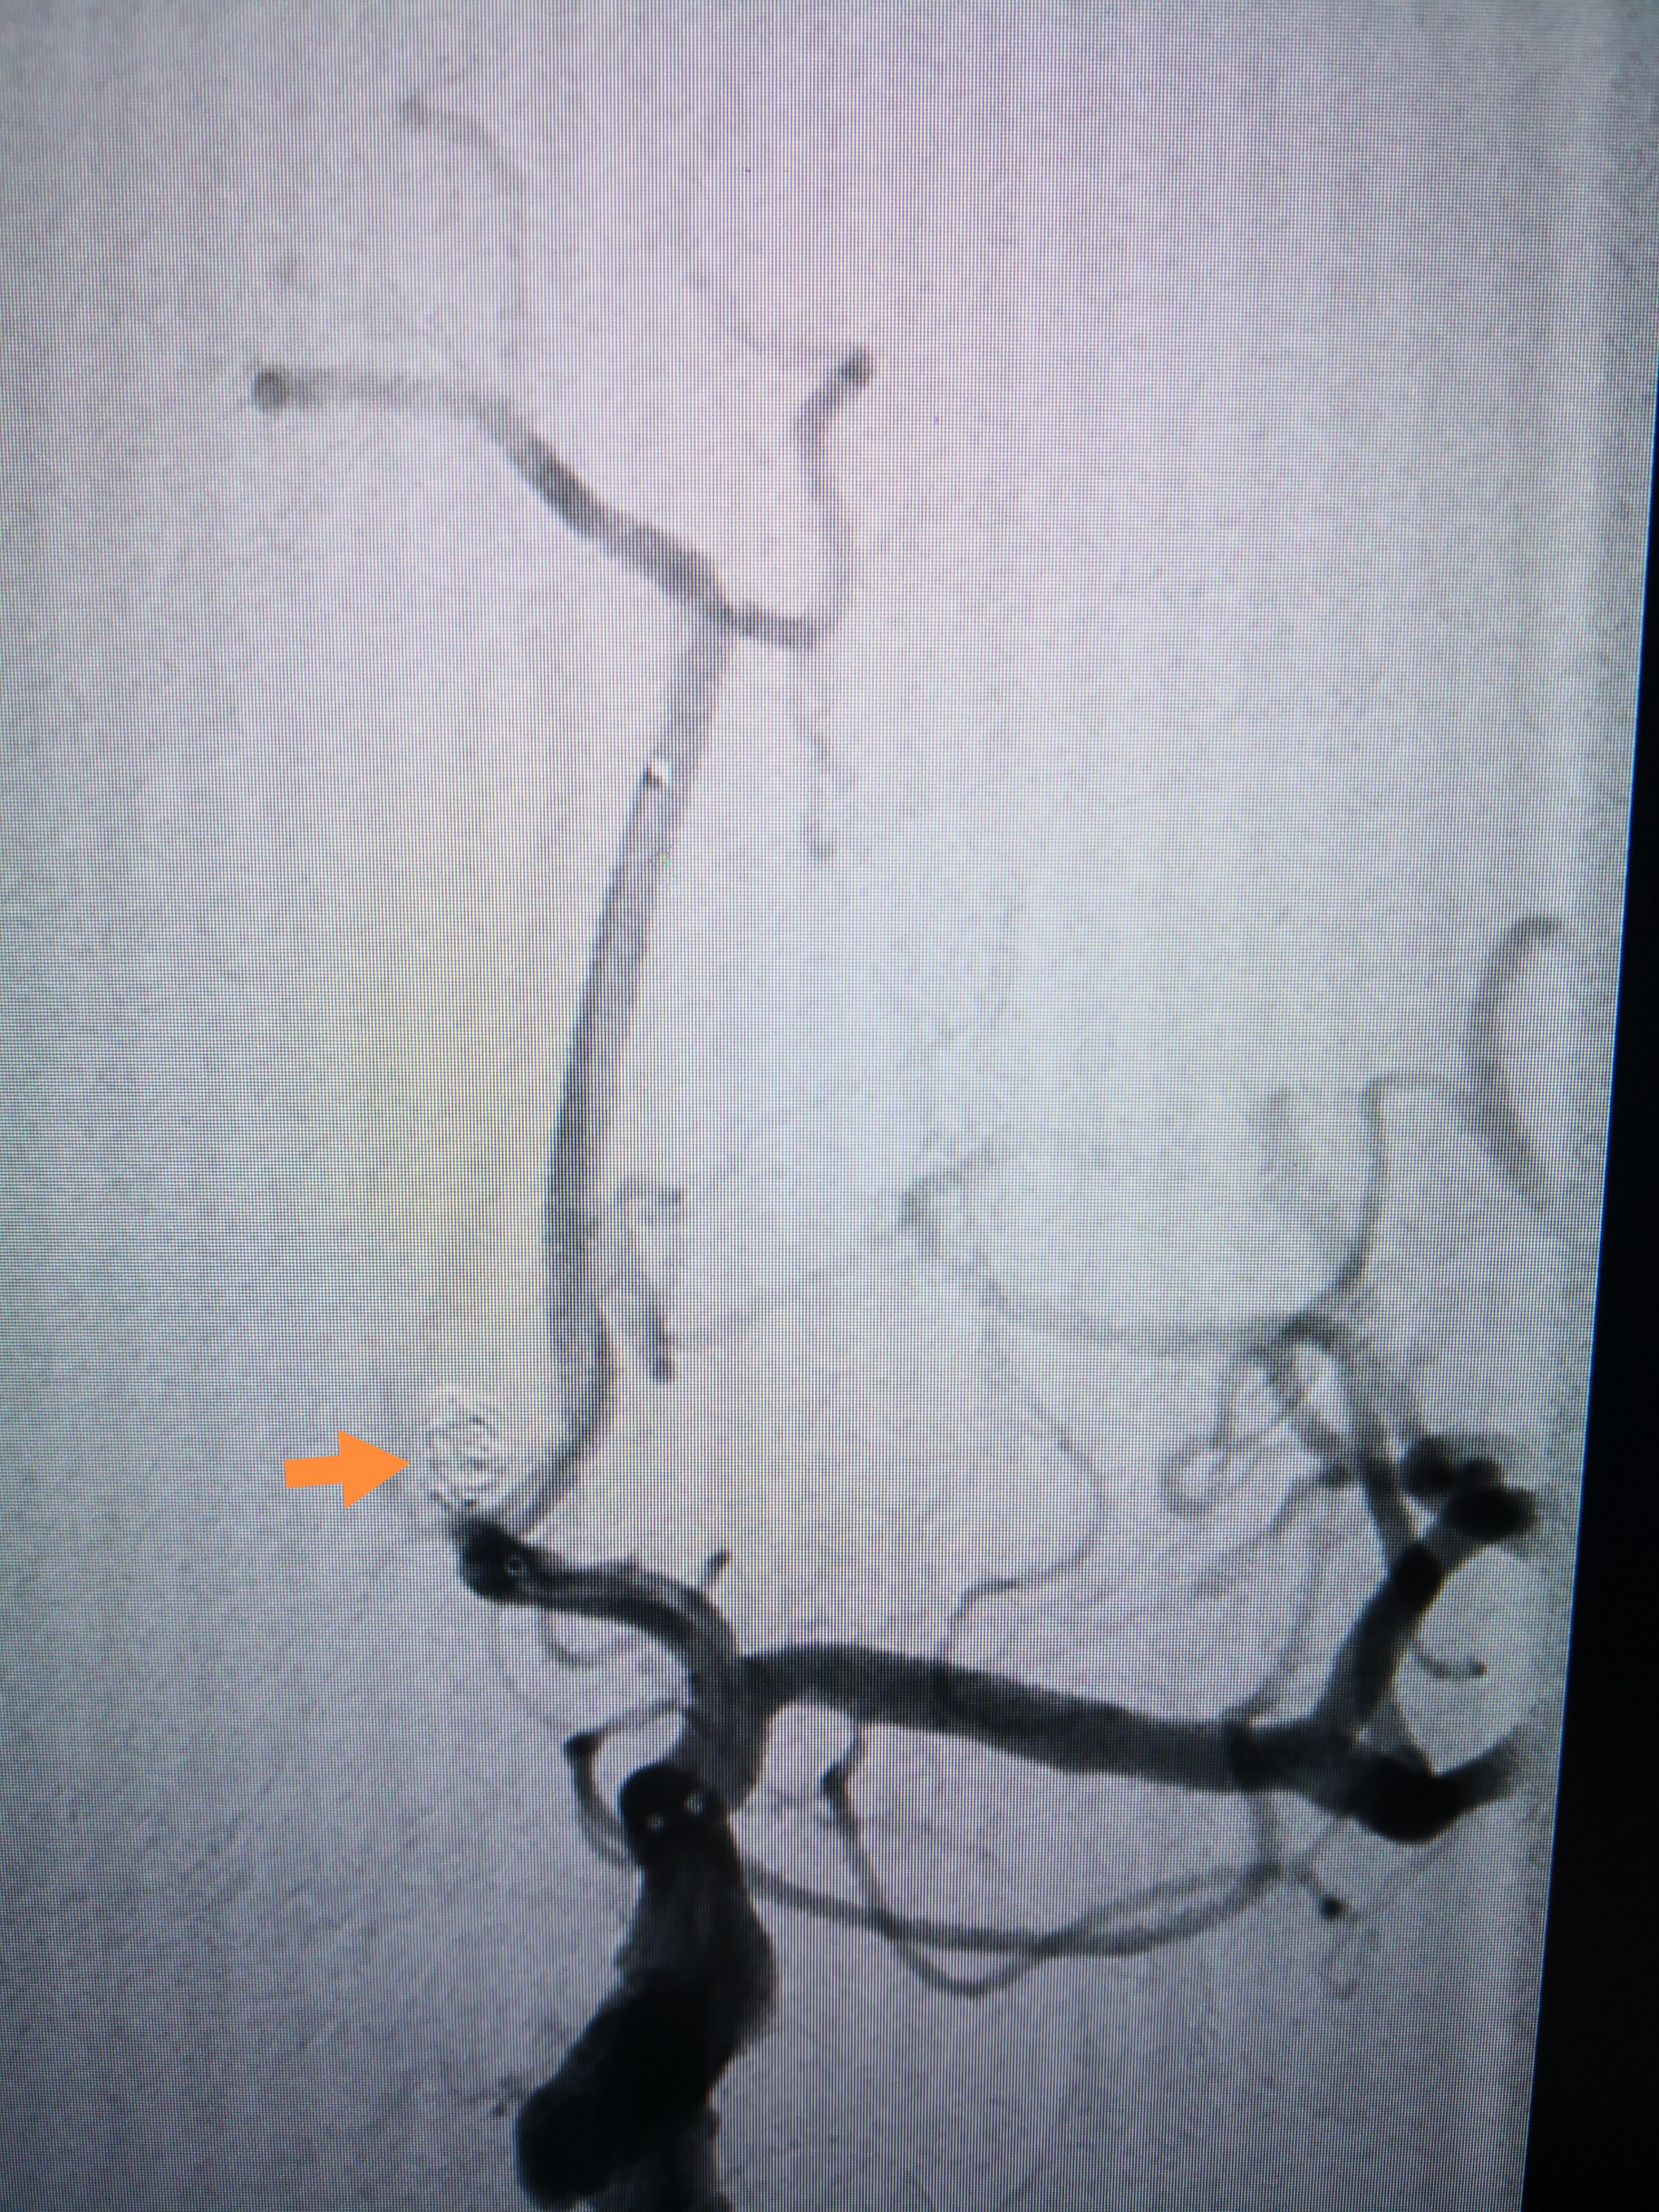

手术前后对比,动脉瘤致密栓塞,载瘤动脉通畅

7月9日,在导管室、麻醉科的全力配合下,由神经外科脑血管病介入团队在全麻下实施了前交通动脉瘤弹簧圈栓塞术。手术中,神经外科介入团队沉稳操作,克服了严重头颈动脉粥样硬化及迂曲的困难,一步步精准操作将中间导管送达指定位置,栓塞微导管小心进入动脉瘤,栓塞弹簧圈缓慢送入动脉瘤腔内。经过2个小时的手术,患者这颗颅内“不定时炸弹”被成功拆除。过程顺利,动脉瘤达到致密栓塞,载瘤动脉通畅。术后第一天为患者实施了腰大池置管,引流血性脑脊液。术后第二天患者神志转清,拔除气管插管,目前正在进一步治疗中。患者家属由衷的表示感谢,特意写了感谢信。